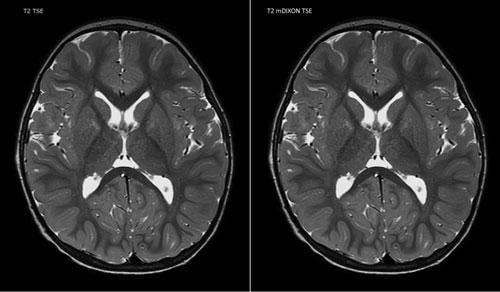

Rather than focusing on particular applications, some RSNA vendors chose to focus on overall image enhancement for their MRI systems. Philips, in collaboration with Dixon Technologies, debuted the mDixon scan sequence for itnTV, which helps simplify and accelerate complicated scans such as the liver.

“mDixon addresses one of the key challenges in MR imaging, which is fat saturation,” Martijn Hartjes, head of MR strategy for Philips, told Freiherr in the itnTV video. “You want to see certain anatomies, and that’s why you want to get rid of the fat.” Hartjes said this is typically done with sequences like SPIR (spectral presaturation with inversion recovery) and STIR (short-TI inversion recovery), “but what you sometimes see is that fat sat fails,” meaning the fat is not completely suppressed from the image. These types of scans can also take longer, Hartjes told itnTV. mDixon resolves both of these issues, offering complete fat suppression while actually reducing the scan time from four minutes to three minutes.